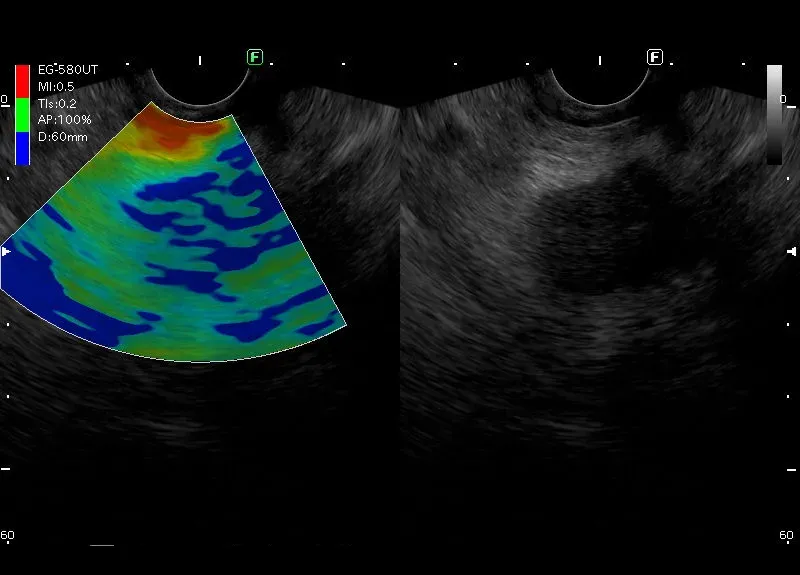

Zmiana położona w głowie trzustki o niejednorodnie obniżonej echogeniczności, nierównych zarysach i wielkości około 23/30mm. W badaniu power doppler widoczny  jest dyskretny przepływ obwodowy. Zmiana kodującej się na niebisko -„zmiana twarda” w elastografii. Całokształt obrazu odpowiada guzowi trzustki.